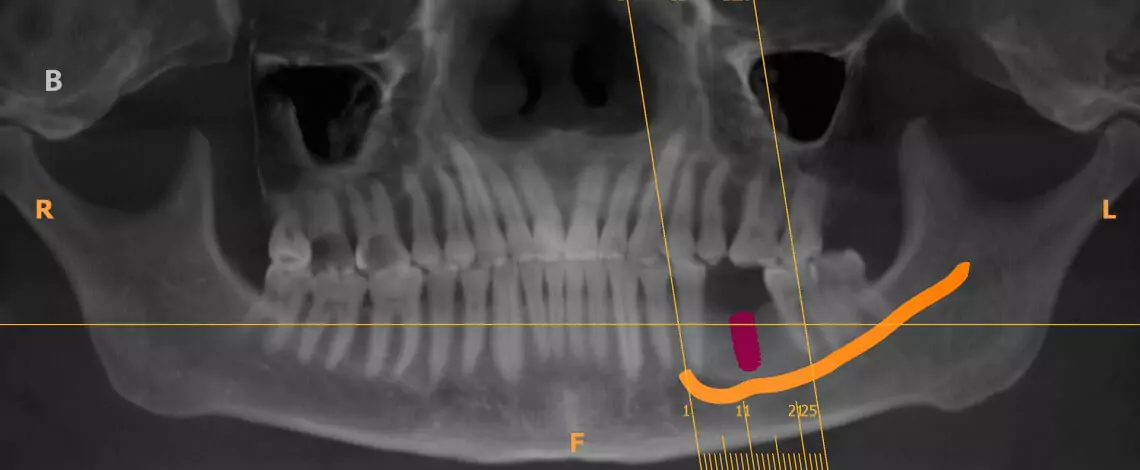

Cone Beam CT (CBCT)

Kodak CS 9300